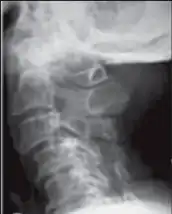

Image,lateral view shows cervical spondylotic myelopathy